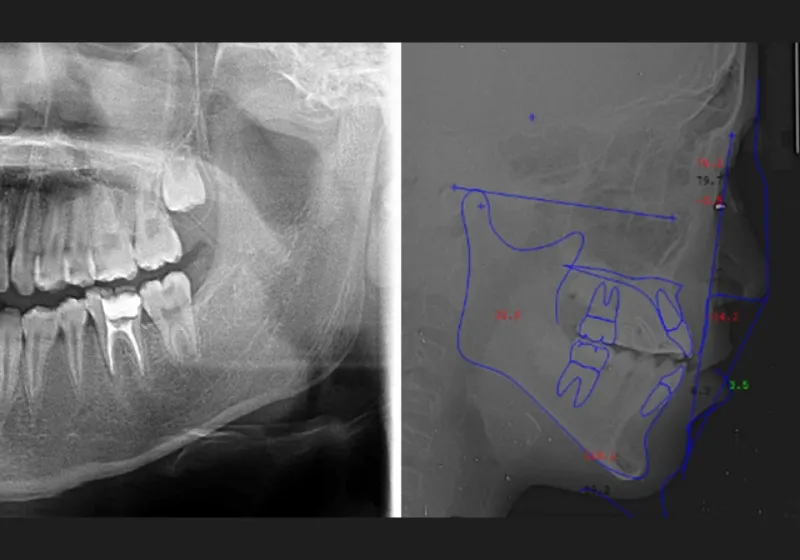

精密検査

口腔内写真やレントゲンの撮影、歯型取りなど、口や顎の状態を詳しく把握するための精密検査を行ないます。さらに、骨の成長状況や身長・体重の増加傾向、永久歯の生えかわりについても確認します。

- Step 03

診断と治療計画の説明、決定

精密検査の情報をもとに、担当の歯科医師が診断し、お子さまの口の状況に適した治療計画を作成します。その後、立案した治療計画の内容や具体的な費用について詳しくご説明します。